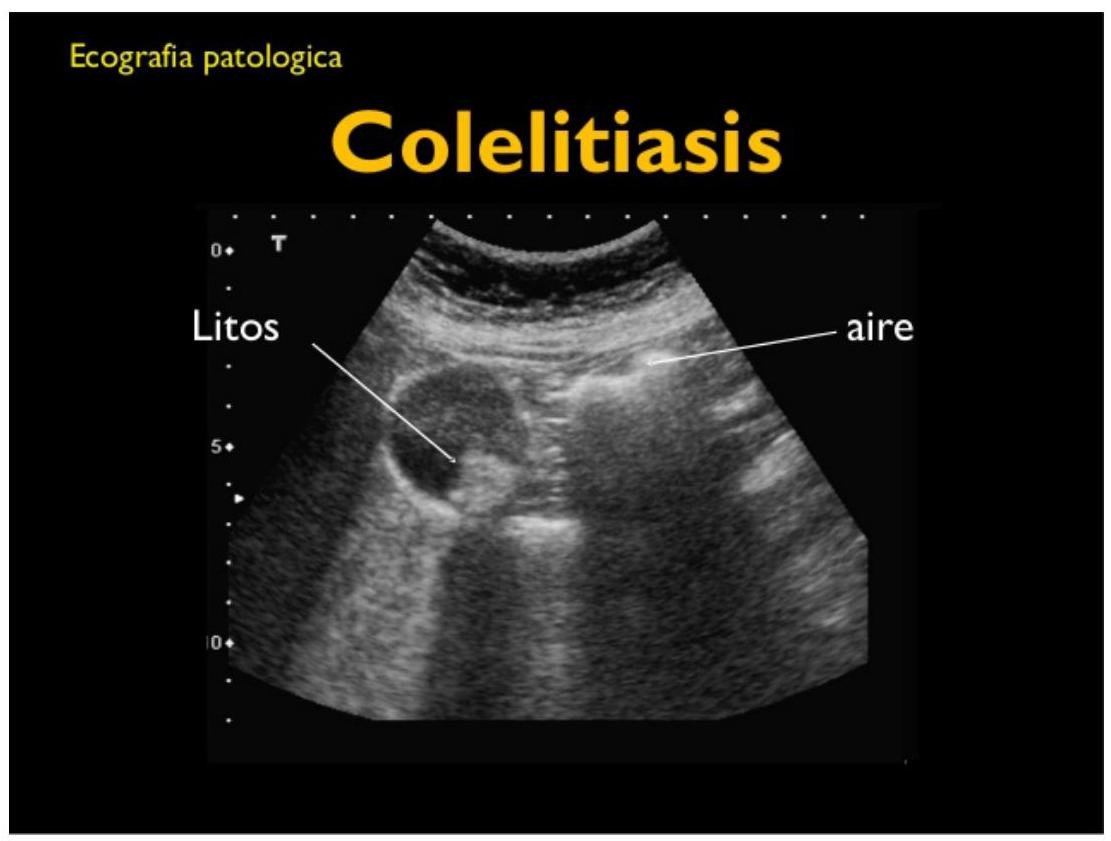

# COLELITIASIS Y COLECISTITIS ## DEFINICIÓN ## COLECISTITIS Es la inflamación de la vesícula biliar ocasionada principalmente por **cálculos (litos)** y con menor frecuencia por **barro (lodo) biliar**, aunque en raras ocasiones ninguna de estas dos está presente. ## COLELITIASIS O litiasis biliar, es la presencia de cálculos dentro de la vesícula biliar. Habitualmente, los cálculos biliares se forman en la vesícula biliar, pero pueden hacerlo a cualquier nivel del tracto biliar. ## COMPOSICIÓN Habitualmente están formados por una mezcla de colesterol, bilirrubinato cálcico, proteínas y mucina. 1. Colesterol (80%) 2. Pigmentarios (común en asiáticos) a. Negros: Bilirrubina, Carbonato, Fosfato, Calcio b. Marrones: Bilirrubinato cálcico, Ac. Palmítico 3. Mixta (la más común) ## ANATOMÍA  ## CHOLECYSTITIS Cystic Duct Gallbladder Gallstones Duodenum Minor Duodenal Papilla  # EPIDEMIOLOGÍA - La colecistitis aguda es una de las principales causas de consulta en el servicio de urgencias y en la consulta externa de cirugía general. - La **colecistitis** se presenta en el 5-20 % de los pacientes con **colelitiasis**. - La colecistitis aguda se presenta con mayor frecuencia en **mayores de 40 años**. - Femenino 2: 1 Masculino. - La colecistectomía es el procedimiento más común realizado por los cirujanos generales. - Los adultos producen entre 500-1,000 ml de Bilis al día. ## FACTORES DE RIESGO | FACTORES DE RIESGO LITOS DE COLESTEROL | FACTORES DE RIESGO LITOS PIGMENTADOS (Bilirrubina con Sales de Calcio o Bilirrubinato) | | :--: | :--: | | - Dislipidemias - **Muy importante** - Female (**mujeres**) - Forty (**mayores a 40 años**) - Fat (**Obesidad**) - Fertility (**Embarazo**) - Fármacos (**fibratos** y la **ceftriaxona**) - Anticonceptivos Orales y Terapia con Estrógenos - Enfermedades del íleon - Enfermedades Hepáticas y Metabólicas (Cirrosis, Diabetes Mellitus) - Antecedentes Familiares de Litiasis Biliar | - Trastornos hemolíticos - Cirrosis - Edad avanzada - Ser Asiático | - Las mujeres tienen el doble de riesgo con respecto a los hombres de presentar colecistitis y colelitiasis. - En cuanto a cirugías realizadas, la relación es Mujer 4 : 1 Hombre. - En el embarazo es frecuente la formación de cálculos de colesterol, normalmente son formas asintomáticas de litiasis biliar y tanto el barro biliar como los cálculos menos de 10 mm desaparecen tras el parto. - Los anticonceptivos orales y la terapia hormonal sustitutiva con estrógenos, en este caso con mayor riesgo en mujeres menores de 40 años y las que reciben una dosis mayor de 50 microgramos de estrógenos. # CLÍNICA Las manifestaciones clínicas de colecistitis y colelitiasis son las siguientes: ## COLELITIASIS Y COLECISTITIS AGUDA NO COMPLICADA 1. Signo de Murphy positivo 2. Masa en cuadrante superior derecho 3. Dolor en cuadrante superior derecho 4. Resistencia muscular en cuadrante superior derecho 5. Náusea y vómito ## COLELITIASIS Y COLECISTITIS COMPLICADA - Vesícula palpable - Fiebre mayor de 39^{\circ} C - Calosfríos - Inestabilidad Hemodinámica ## COLELITIASIS Y COLECISTITIS + PERFORACIÓN DE VESÍCULA CON PERITONITIS Se debe sospechar con los siguientes datos: | - Aumento dolor forma súbita | - Taquipnea | | :-- | :-- | | - Signos de irritación peritoneal difusa | - Acidosis Metabólica | | - Distensión abdominal | - Hipotensión | | - Taquicardia | - Choque. | ## CLASIFICACIÓN | GRADO I - LEVE | Colecistitis aguda en paciente saludable y sin disfunción orgánica. Cambios inflamatorios leves en la vesícula biliar. Colecistectomía segura con bajo riesgo operatorio. | | :--: | :--: | | GRADO II - MODERADA | Colecistitis aguda acompañada de las siguientes condiciones: - Leucocitosis Elevada (>18,000) - Masa palpable en cuadrante superior derecho - Duración del cuadro clínico >72 horas - Inflamación local (peritonitis biliar, absceso perivascular, hepático, enfisema). Requiere Internamiento + Antibióticos IV. | | GRADO III - GRAVE | Colecistitis aguda acompañada por **Daños a órgano o sistema**: - Disfunción cardiovascular (hipotensión que requiere dopamina o dobuta) - Disfunción neurológica (disminución del nivel de conciencia) - Disfunción respiratoria ( PaO2/Fio2 promedio <300) - Disfunción renal (oliguria, Creatinina >2.0 ) - Disfunción hematológica (plaquetas <100,000 ) | # DIAGNÓSTICO Considerar diagnóstico con: Signo o Síntoma Local + Signo Sistémico + Estudio de Imagen positivo. ## LABORATORIO No existen pruebas de laboratorio específicas para colecistitis aguda, sin embargo, las siguientes pueden tener utilidad: - Biometría Hemática: puede aparecer leucocitosis. - Proteína C Reactiva: puede hallarse elevada y es de utilidad para confirmar proceso inflamatorio. - Otras: Bilirrubinas, BUN, Creatinina, Tiempo de Protrombina, Amilasa (para identificar complicaciones como Coledocolitiasis, no confundir con Pancreatitis [se necesita el triple de su valor]). - Hemocultivo/Cultivo: deberá ser solicitado en presencia de fiebre y sospecha de cuadro infeccioso para seleccionar el agente microbiano. ## ESTUDIO DE IMAGEN ## 1ra elección: Ultrasonido - Ante la sospecha de colecistitis o colelitiasis aguda es la prueba no invasiva de primera elección. - El USG abdominal es positivo en el 98 % de los casos (sensibilidad). ## Hallazgos que reporta el USG: - Engrosamiento de la pared vesicular +5 mm - Líquido perivesicular - Signo de Murphy ultrasonográfico positivo - Alargamiento vesicular 8 cm axial y 4 cm diametral - Lito encarcelado - Imagen de doble riel - Sombra acústica posterior (presencia de lito) - Ecos intramurales  ## GAMMAGRAFÍA BILIAR (Escintografía) Tiene sensibilidad del 97 % y se debe solicitar cuando la clínica y la ecografía no fueron concluyentes. ## TOMOGRAFÍA AXIAL COMPUTARIZADA - Engrosamiento de pared vesicular - Colecciones líquidas perivasculares - Alargamiento vesicular - Áreas de alta densidad en el tejido graso perivesicular ## RESONANCIA MAGNÉTICA - Signos de pericolecistitis con imágenes de alta densidad - Alargamiento vesicular - Engrosamiento de pared vesicular # GAMMAGRAFÍA VÍA BILIAR CON TC-HIDA - Exclusión vesicular - Signo de Rim (aumento de la radioactividad alrededor de la fosa vesicular)  ## DIAGNÓSTICO DIFERENCIAL Ante el reporte negativo de las pruebas diagnósticas para la **Colelitiasis y Colecistitis** se deberá realizar el diagnóstico diferencial con alguna de las siguientes entidades: - Úlcera péptica perforada - Apendicitis aguda - Obstrucción intestinal - Pancreatitis aguda - Cólico renal o biliar - Colangitis aguda bacteriana - Pielonefritis - Hepatitis aguda - Hígado congestivo - Angina de pecho - Infarto de miocardio - Rotura de aneurisma aórtico - Tumores o abscesos hepáticos - Herpes zoster - Síndrome de Fitz-Hugh-Curtis # TRATAMIENTO ## FARMACOLÓGICO Estará reservado para los pacientes en situaciones especiales por alto riesgo quirúrgico o que rechazan cirugía. ## 1ra elección: Ácido Ursodesoxicólico / Ácido Quenodeoxicólico - Para la disolución de los cálculos biliares el tratamiento de elección son los ácidos biliares orales. - Debe emplearse por un periodo de 1-2 años. - También se usa como coadyuvante cuando se realiza litotricia, mayor efectividad de destrucción. ## AINES ## 1ra elección: Diclofenaco 75 mg IM - En pacientes con cólico biliar es recomendable para prevenir aparición de colecistitis aguda. - Si ya existe colecistitis aguda, no demuestran remisión de la enfermedad. ## OPIOIDES - En presencia de dolor intenso se puede manejar con Meperidina. ## ANTIBIÓTICO La elección dependerá de la susceptibilidad local por el antibiograma, la administración previa de un antibiótico, de la disfunción renal o hepática y de la gravedad de la colecistitis. (Guías Sanford). | Colecistitis Grado I | 1ra elección: Un solo antibiótico A. Fluoroquinolonas Orales (Levofloxacino o Ciprofloxacino) B. Cefalosporinas Orales (Cefotiam, Cefcapene) C. Penicilinas Amplio Espectro (Ampicilina con Sulbactam) | | :--: | :--: | | Colecistitis Grado II | 1ra elección: Doble Antibiótico A. Penicilinas de Amplio Espectro (Pipe/Tazo o Ampicilina con Sulbactam) B. Cefalosporinas de segunda generación (Cefmetazole, Cefotiam, Oxacefem, Flomoxef) | | Colecistitis Grado III | 1ra elección: Doble antibiótico más potente. A. Cefalosporinas de 3ra y 4ta generación (Ceftriaxona, Ceftazidima, Cefepime, Cefozopran, Cefoperazona con Sulbactam) B. Monobactámicos (Aztreonam) Metronidazol cuando se detecta o se sospecha de anaerobios (casos complicados). | MICROORGANISMOS: La bilis es estéril; una intervención, manipulación o estasis de ella aumenta la probabilidad de contaminación: **E. coli, Klebsiella, Enterobacter** (**Gram negativos**). # LITOTRICIA La litotricia + disolutos orales (Sales biliares) no ofrecen suficiente evidencia para ser indicado como tratamiento en presencia de litiasis vesicular y no está aprobado por la FDA como tratamiento definitivo, pero la GPC recomienda realizarla en las siguientes situaciones: ## Indicaciones para litotricia - Pacientes con **litiasis única**. - **No** calcificada. - Diámetro de 20-30 mm. ## Contraindicaciones para litotricia - Pancreatitis - Alteraciones de la coagulación - Quistes o aneurismas en el trayecto de las ondas ## QUIRÚRGICO ## 1ra elección: Colecistectomía Esta puede ser realizada por laparotomía o laparoscopía. | Colecistectomía Temprana | Se realiza 1 - 7 días después del ataque inicial. | | :--: | :--: | | Colecistectomía Tardía | Se realiza 2 - 3 meses después del ataque inicial. | ## COLECISTECTOMÍA LAPAROSCÓPICA Se prefiere a la abierta por: menor mortalidad, menores complicaciones, menor estancia hospitalaria, reincorporación laboral rápida. ## FACTORES QUE DIFICULTAN CIRUGÍA LAPAROSCÓPICA: - Masculinos - Cirugía abdominal previa - Presencia o antecedentes de Ictericia - Colecistitis en fase avanzada - Infecciones graves | COMPLICACIONES LAPAROSCÓPICA | - Lesión del conducto biliar - Lesión del intestino - Lesión hepática - Infección de sitio quirúrgico | | :--: | :--: | | COMPLICACIONES ABIERTA | - Infecciones - Íleo - Hemorragia intraperitoneal - Atelectasia - Trombosis de venas profundas - Infección del tracto urinario | ELECCIÓN DE LA TÉCNICA QUIRÚRGICA | GRADO I - LEVE | 1ra elección: Colecistectomía Temprana por Laparoscopía. | | :--: | :--: | | GRADO II - MODERADA | 1ra elección: Colecistectomía Temprana por Laparoscopía, sin embargo, depende de la experiencia del cirujano para el abordaje. Si presenta inflamación grave de la vesícula se recomienda un drenaje temprano que puede ser quirúrgico o percutáneo. Si se hay inflamación grave de la vesícula la colecistectomía temprana puede ser difícil, se recomienda posponer cirugía hasta que disminuya la inflamación. | | GRADO III - GRAVE | 1ra elección: Colecistectomía Laparoscópica, sin embargo, dependerá del cirujano y su pericia instrumental. - Manejo urgente de la falla orgánica - Tratamiento de inflamación local - Drenaje de vesícula - Se realiza cirugía cuando las condiciones generales mejoren. | # CPRE La combinación de extracción de litos por endoscopía durante una colangio - pancreatografía retrógrada endoscópica y la colecistectomía laparoscópica es de utilidad en el tratamiento. El intervalo entre estos dos procedimientos es de pocos días, debe hacerse en el mismo tiempo intrahospitalario. ## SEGUIMIENTO - Se deberá realizar por el servicio de cirugía hasta su egreso hospitalario. - Será evaluado una semana después del egreso en la consulta externa de cirugía general. - Se valorará alta de servicio y contrarreferencia a primer nivel. # RECUPERACIÓN ## ESTANCIA HOSPITALARIA | COLECISTECTOMÍA LAPAROSCÓPICA | 1 día de estancia es suficiente. | | :-- | :-- | | COLECISTECTOMÍA ABIERTA NO COMPLICADA | 2-3 días postquirúrgicos. | ## INCAPACIDAD | TÉCNICA | TIEMPO MÍNIMO | ÓPTIMO | MÁXIMO | | :-- | :--: | :--: | :--: | | LAPAROSCÓPICA | 10 | 14 | **21** | | LAPAROSCÓPICA NO COMPLICADA | 14 | 21 | **28** | | ABIERTA | 14 | 21 | **28** | | ABIERTA COMPLICADA | 21 | 28 | **45** | # ALGORITMO ABORDAJE